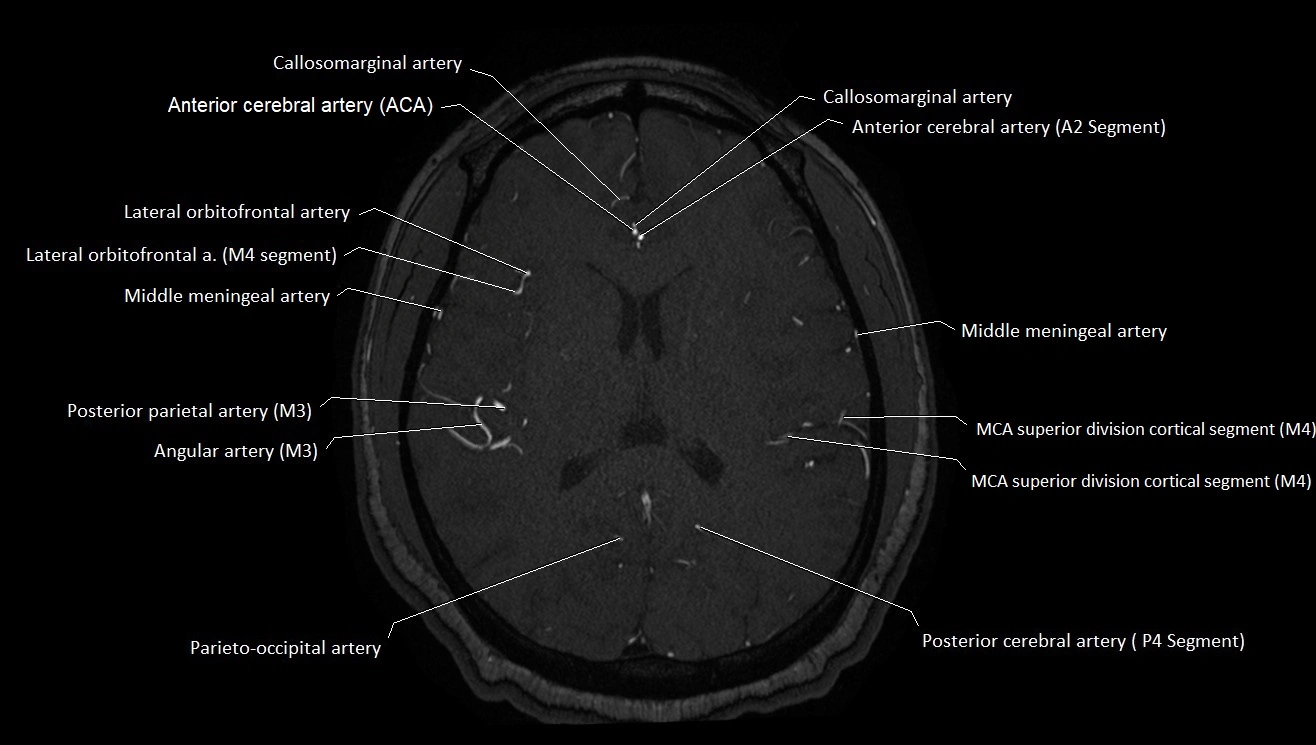

MRA (Magnetic Resonance Angiography):

• Flow-related enhancement makes the AChA appear as a bright, linear vascular signal against suppressed background

• High sensitivity for origin and proximal course; distal branches may be too small to resolve

• Detects stenosis, occlusion, aneurysm, AVM feeders

MRI images

image